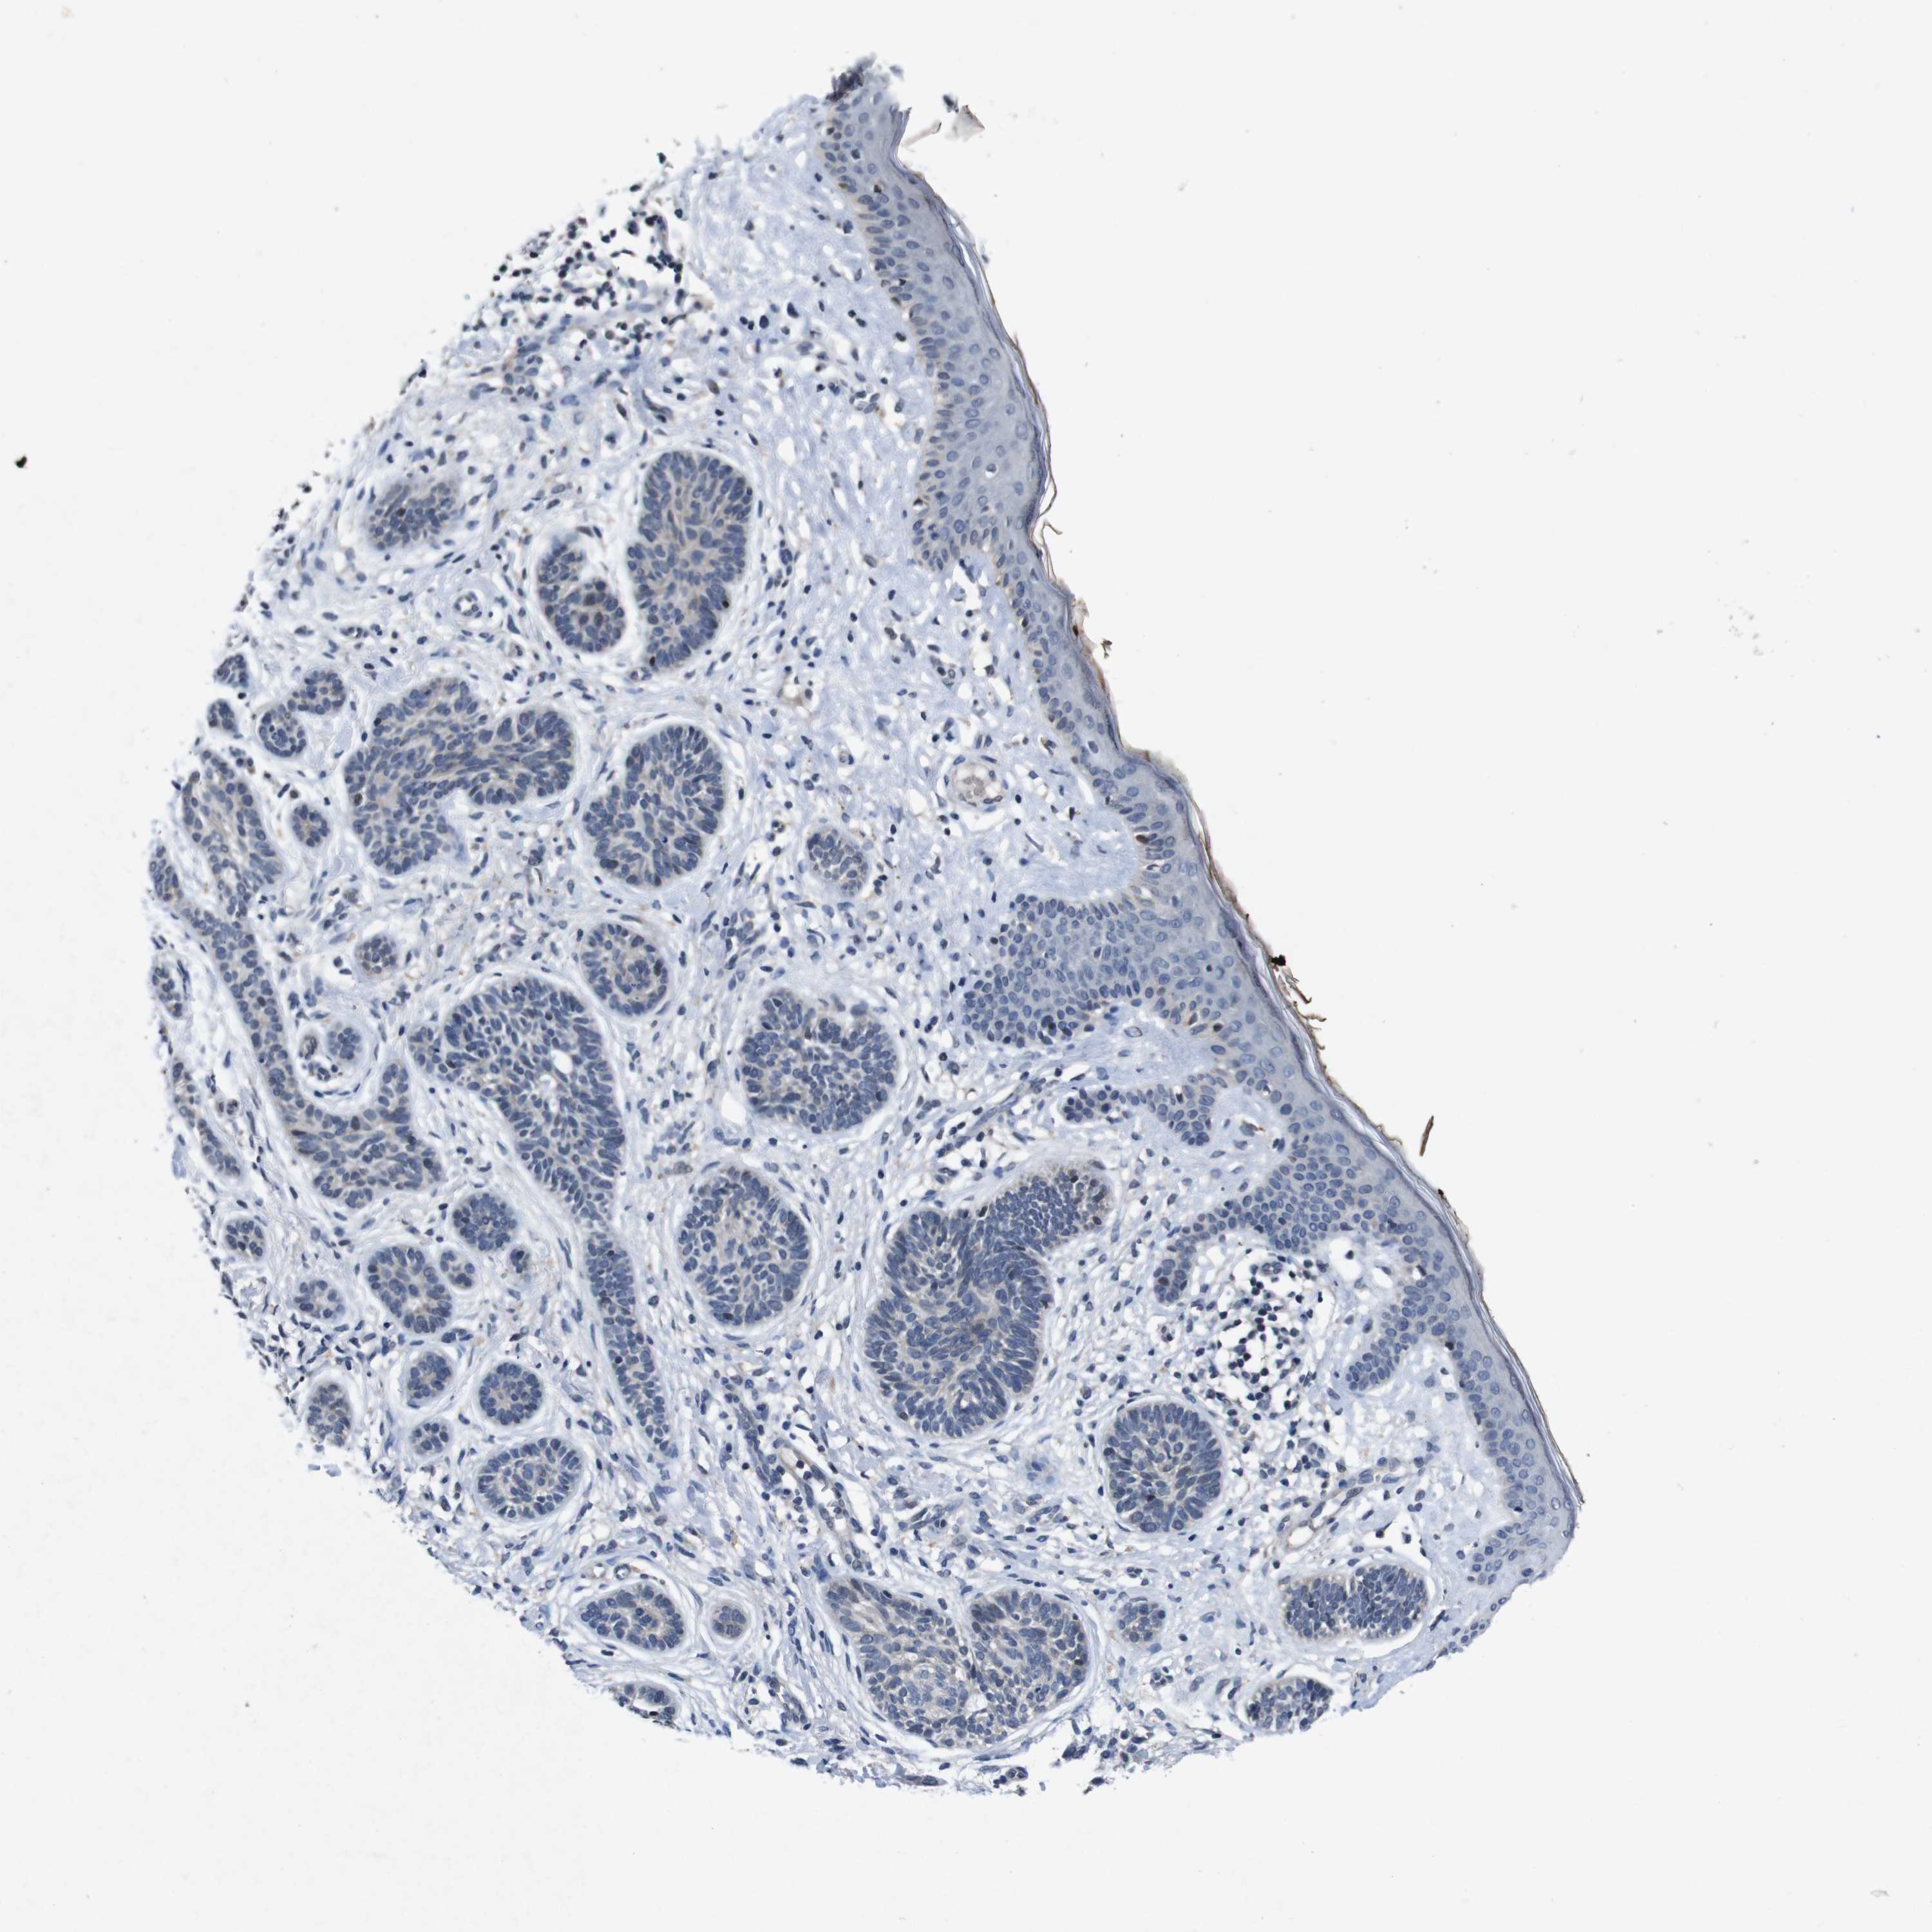

SKIN CANCER - Protein expressioni

A mouse-over function shows sample information and annotation data. Click on an image to view it in a full screen mode. Samples can be filtered based on level of antibody staining by selecting one or several of the following categories: high, medium, low and not detected. The assay and annotation is described here.

Antibody stainingi

Antibody staining in the annotated cell types in the current human tissue is reported as not detected, low, medium, or high, based on conventional immunohistochemistry profiling in selected tissues. This score is based on the combination of the staining intensity and fraction of stained cells.

Each image is clickable and will lead to virtual microscopy that enables deeper exploration of all samples and also displays staining intensity scores, fraction scores and subcellular localization as well as patient and tissue information for each sample.

Antibody HPA026441

Basal cell carcinoma